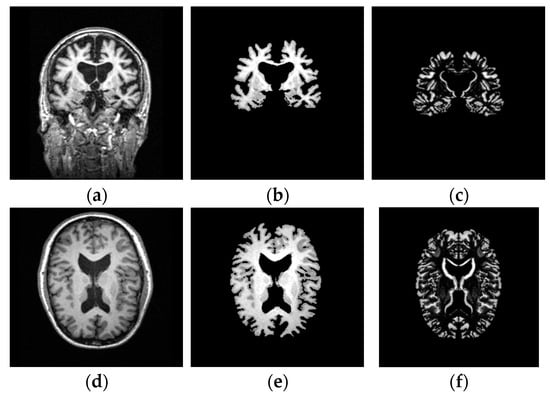

3.2.1. Image Preprocessing

3.2.2. Detection of Image Asymmetry